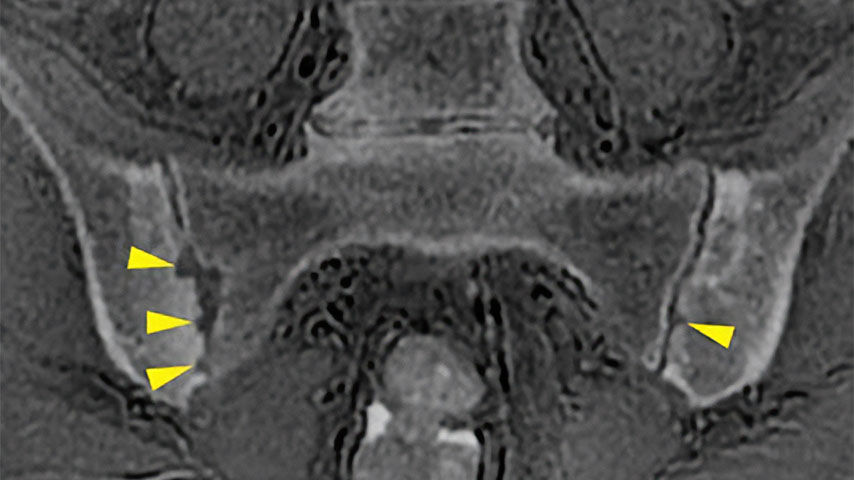

One-stop Orthopedic Shop

Provides cortical bone information co-registered with the soft tissue series

CT-like Image Contrast